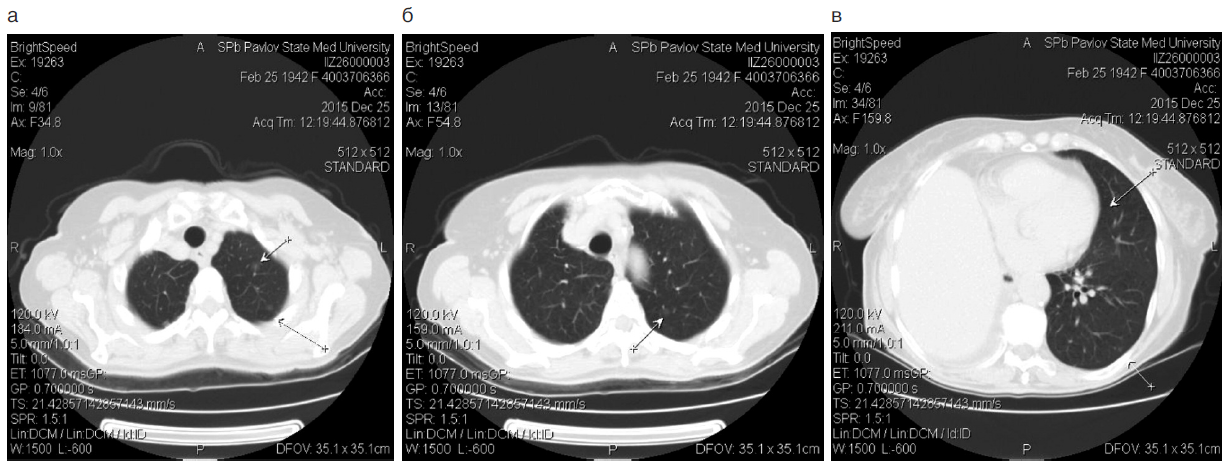

В феврале 2015 г. обратилась к врачу по поводу появления сухого кашля. При флюорографии выявлены очаговые образования правого легкого. При компьютерной томографии (КТ) выявлены периферическая опухоль нижней доли правого легкого, метастазы в среднюю долю и лимфоузлы средостения.

Через 3 мес после операции, в сентябре 2015 г., при контрольной КТ (рис. 1) выявлена прогрессия заболевания – появление метастазов в обоих легких, плеврит справа.

Рис. 1. КТ больной З., 73 года, ноябрь 2015 г.

Fig. 1. Computed tomography of patient Z., 73 years old, November 2015.